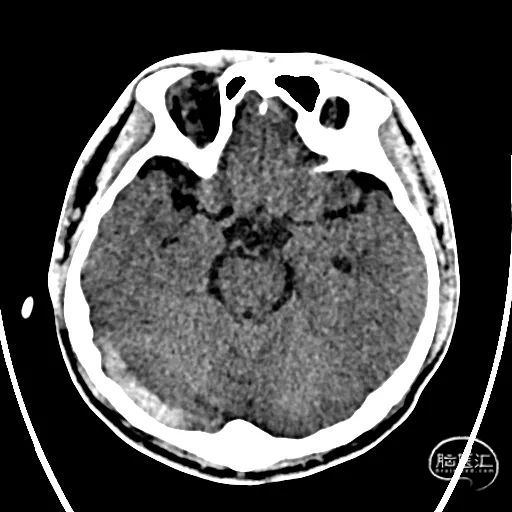

术前CTA/CTP检查,动脉成像未见明显异常,平扫CT可见右侧横窦区域高密度、左侧顶叶片状高密度,窦汇区域、上矢状窦区域高密度充盈。随后紧急性头颅MRV检查,MRV提示上矢状窦及右侧横窦区域不显影。

图注1:1A/1B 平扫CT可见右侧横窦、窦汇区域高密度,额顶叶片状高密度灶

1C 通路CTA检查动脉像未见特殊

1D/1E MRV冠状位及侧位可见上矢状窦及右侧横窦消失,左侧横窦乙状窦部分显影